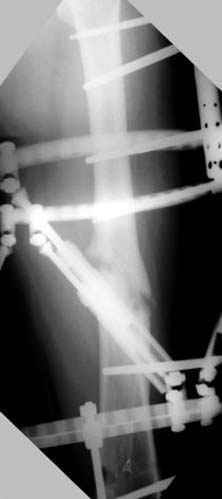

Несколько снимков из моей коллекции, чтобы разьяснить, почему мы до сих пор делаем различные варианты остеотомии.

N3 рисунок окончательный снимок, после операции моя рентгенограмма должен выглядеть примерно как эта картина. На N4 снимке клин перед удалением; N5 послеоперации 3 нед.; N6 окончательная рентгенограмма.

Отправитель: Djoldas Kuldjanov 23 Ноябрь 2004, 18:21

пластическая модель; и коррекция бедра аппаратом Илизарова.

Почему не замена гвоздя с рассверливанием, а аппарат?

Отправитель: Alexander Chelnokov 23 Ноябрь 2004, 21:29

Попробую угадать - была инфекция?

хотя даже если бы и инфекция , то nail exchange с рассверливанием канала - вариант дебрайдмента) Я думаю, что последовательность развития событий:

Узкий к-м канал - тонкий гвоздь- усталостный перелом дистальных винтов - развитие нестабильности и как ее результат остеолиз вокруг гвоздя - деформация анатомической оси бедра. Похоже, что я понял почему аппарат, а не новый гвоздь:-)

ЕТ - Изначально костно-мозговой канал бедра был узкий, дальнейшее его рассверливание ещё больше скомпрометирует прочность бедра( латеральный кортекс дистального отломка уже истончен), приведет к дефекту наружной стенки - хотя это только мои догадки - хотелось бы знать мнение Джолдаса о выбранной тактике.